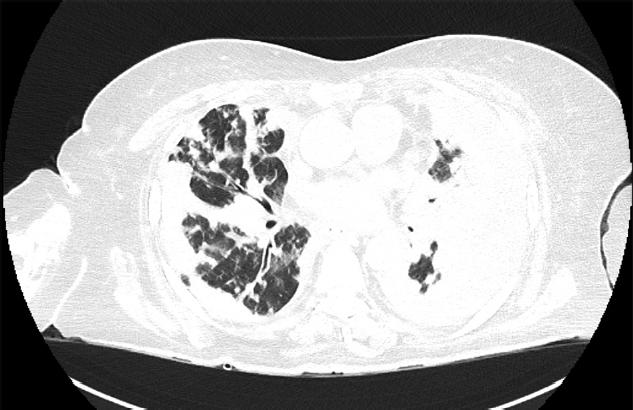

Chest X-ray at second presentation. Progression of opacities with increased pleural effusion volume.

One week after discharge, the patient returned to the emergency department after an accidental fall. Chest radiography now showed progression of the pulmonary lesions and reaccumulation of left pleural effusion (Figure 3). She was readmitted to the pulmonology department, where she received targeted antibiotic therapy per antibiogram (vancomycin 1 g every 12 hr for 10 days) and systemic corticosteroids; repeated thoracentesis evacuated serous-citrine fluid with similar cytologic results (inflammatory pleural effusion). Spirometry performed at discharge revealed severe mixed ventilatory dysfunction, and a repeated 6MWT showed dynamically low values. An autoimmune antibody panel and advanced pulmonary function tests (Diffusing Capacity of the Lungs for Carbon Monoxide – DLco and body plethysmography) were recommended, as well as repeating the chest CT.